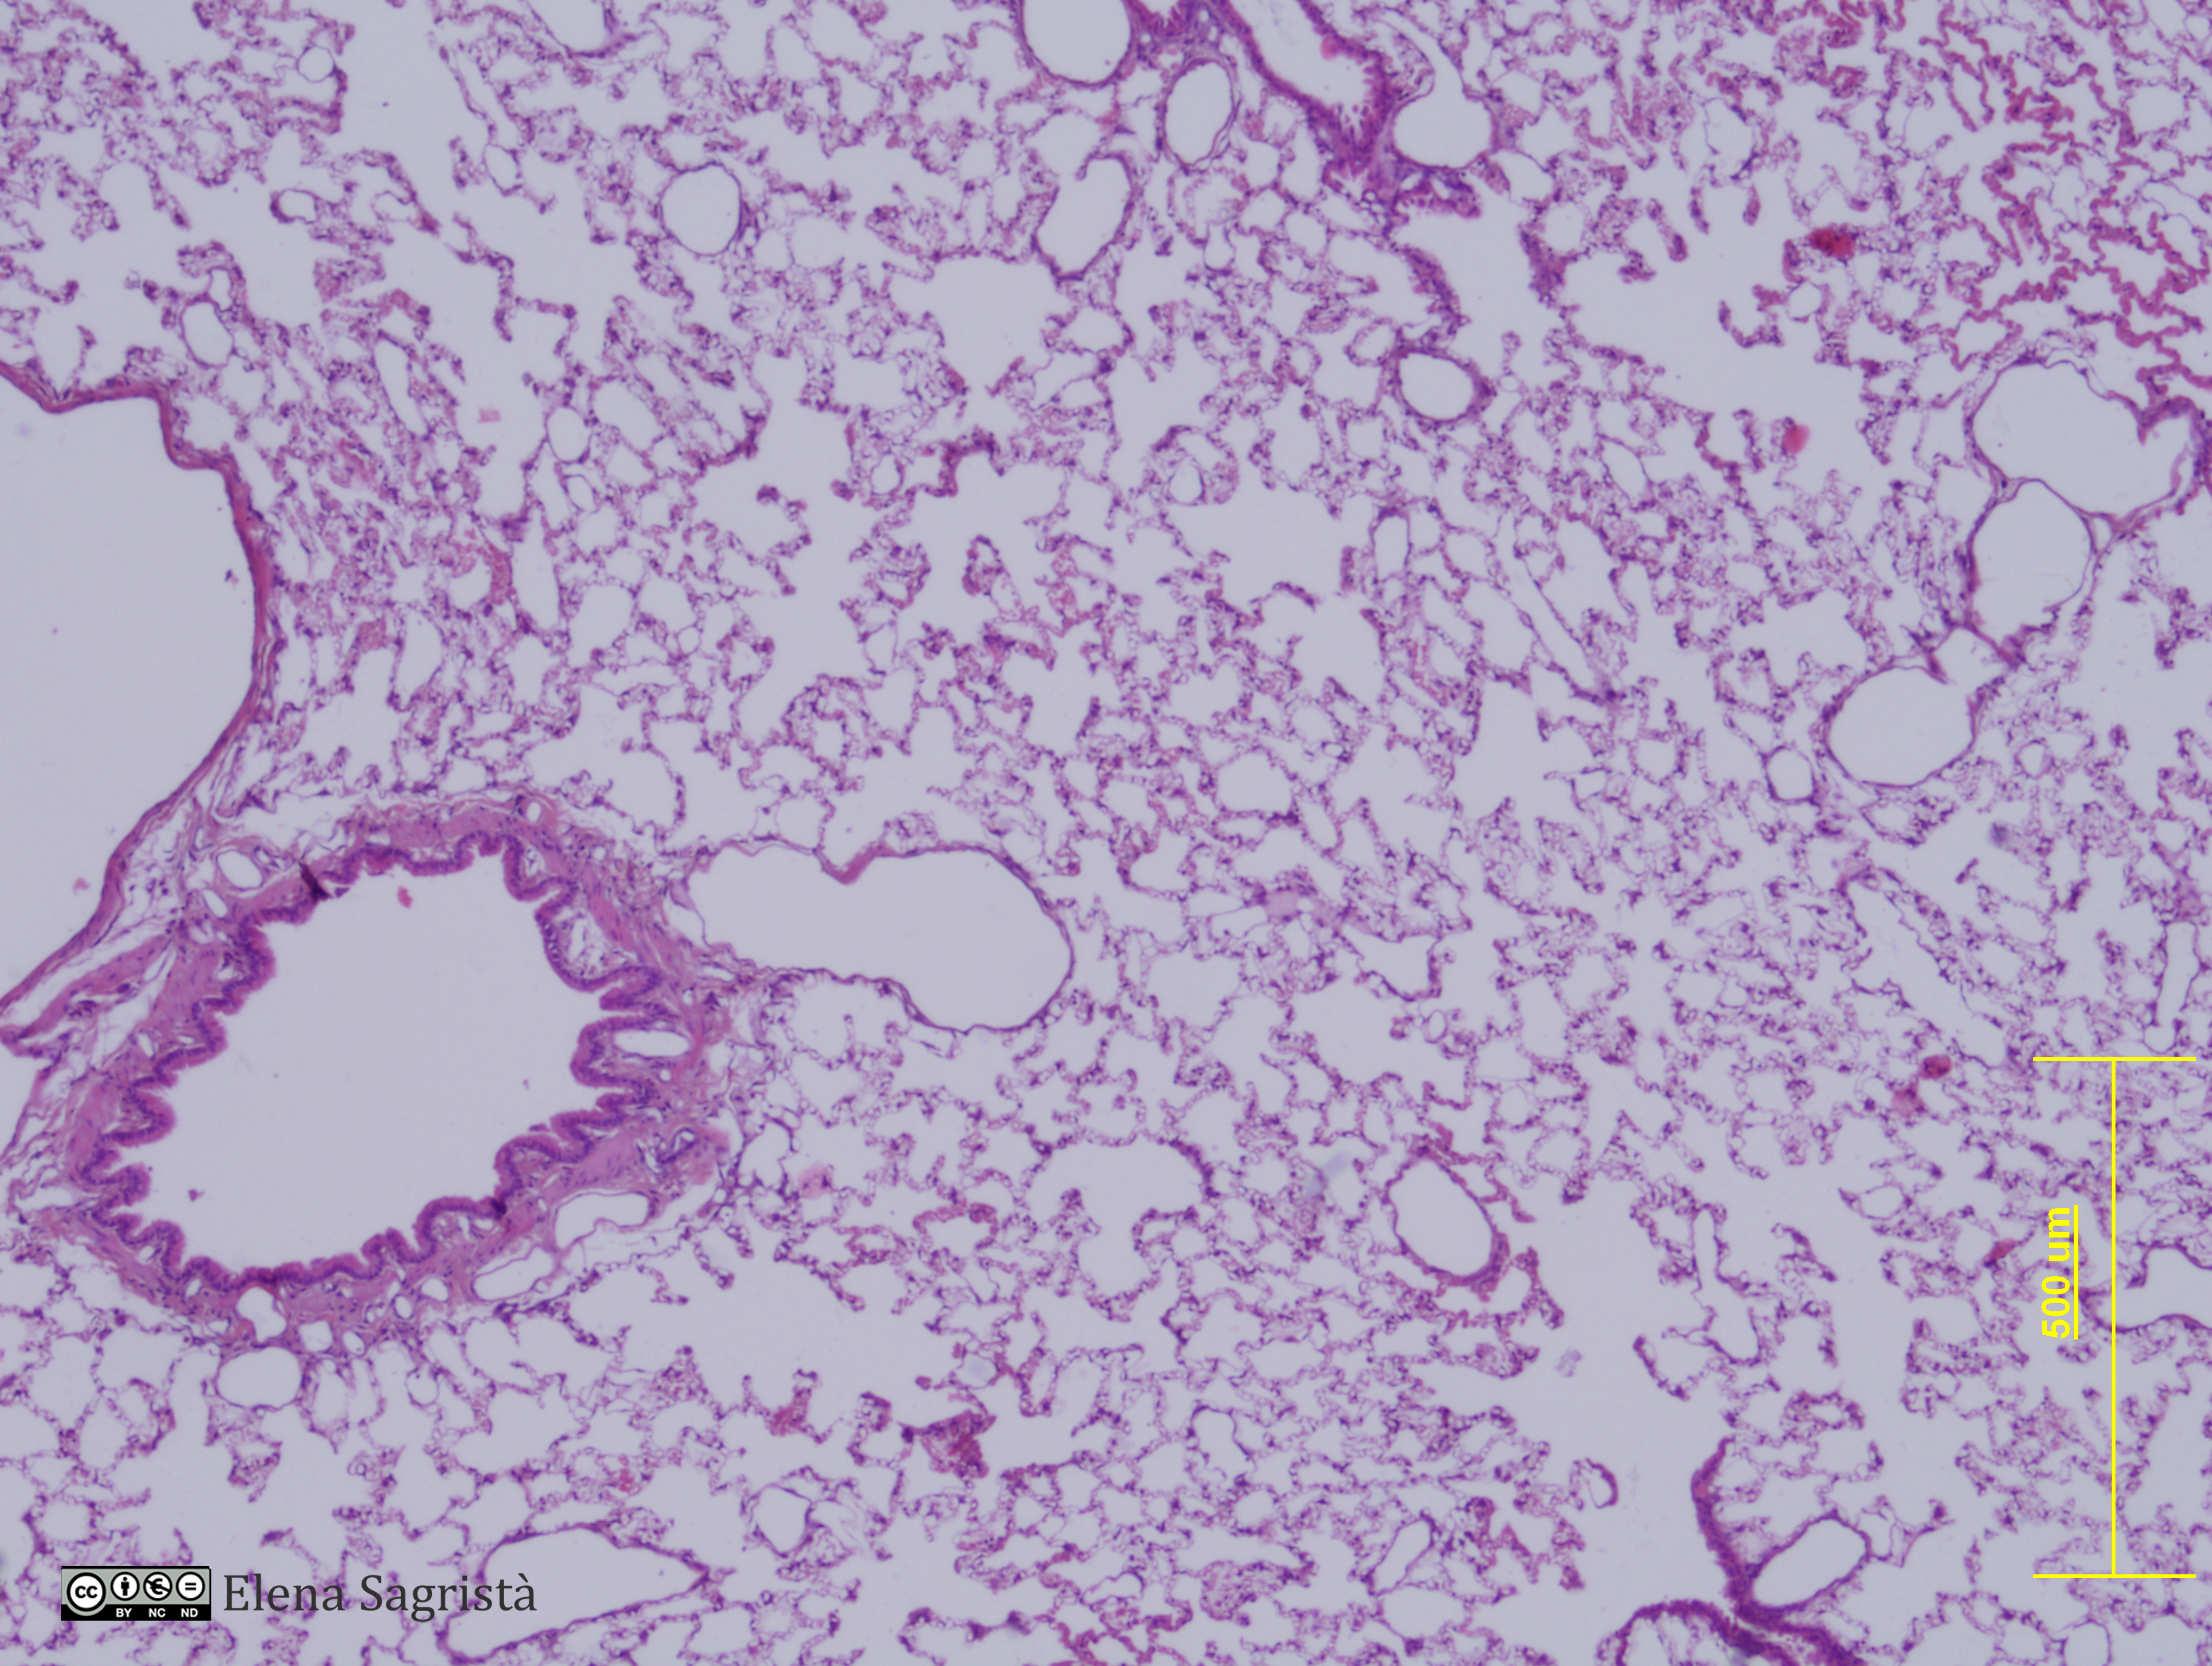

Histologia imatges: 13 Pulmó

Imatges de preparacions histològiques de Pulmò. Microscopia òptica.